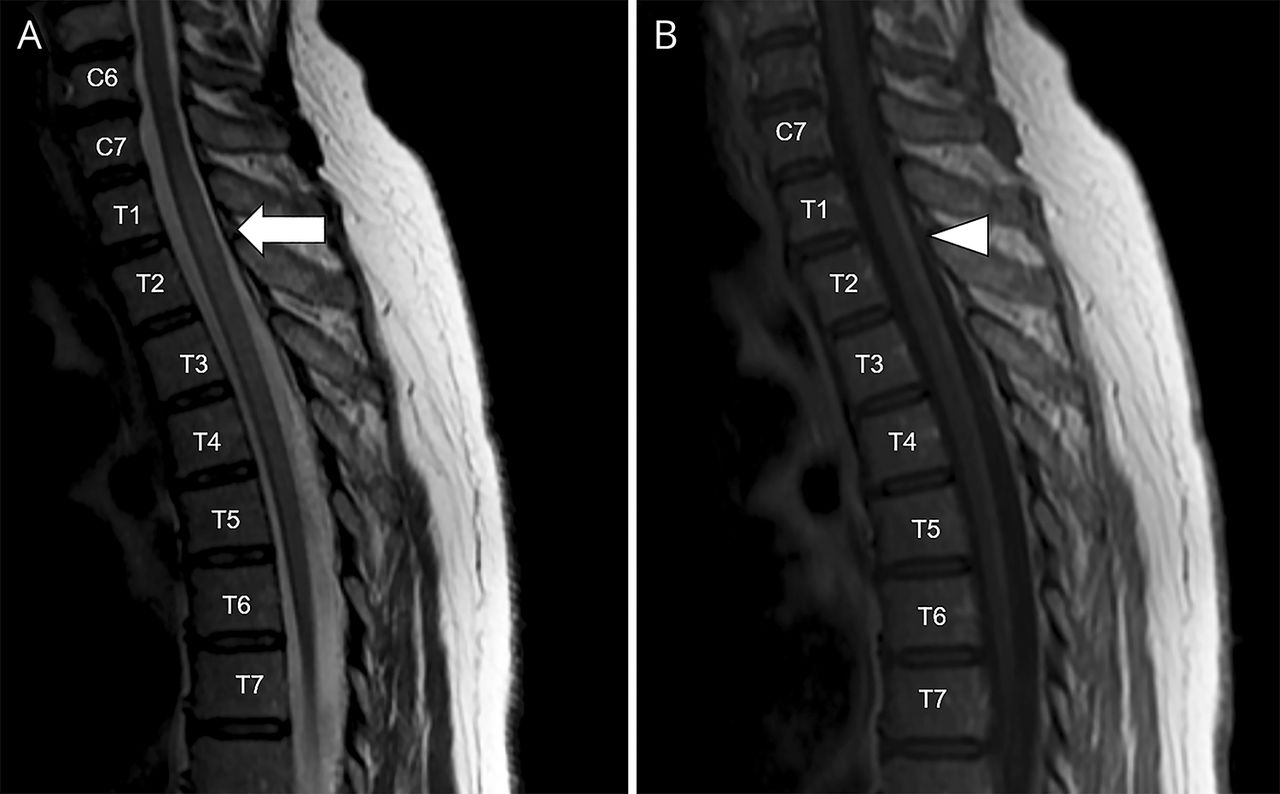

改变表面和深部感觉下肢与轻快的下肢深部腱反射和括约肌障碍本地化脊髓的赤字。没有力量的赤字进一步表明主要的后定位病变。脊髓的核磁共振显示2 T2 / fluid-attenuated反转恢复hyperintense,中央髓病变,从C2 C4和从C7到T7 (图,一个)。Postgadolinium T1序列显示薄,纵广泛,单纯对比度增强(CE)在C2-C3 T1-T6级别(图B)。脑MRI是不起眼的。脑脊液检查显示,蛋白质浓度轻微海拔(68 mg / dL,正常范围- 40 mg / dL),与正常的葡萄糖和没有细胞。血细胞计数、肝酶,血清肌酐,甲状腺功能正常范围内。

(一)脊髓MRI显示,在矢状T2序列,hyperintense,中央髓损伤,延长从C7到T7(箭头所指)。(B) Postgadolinium T1序列显示薄,纵广泛,单纯对比度增强T1 T6水平(箭头)。